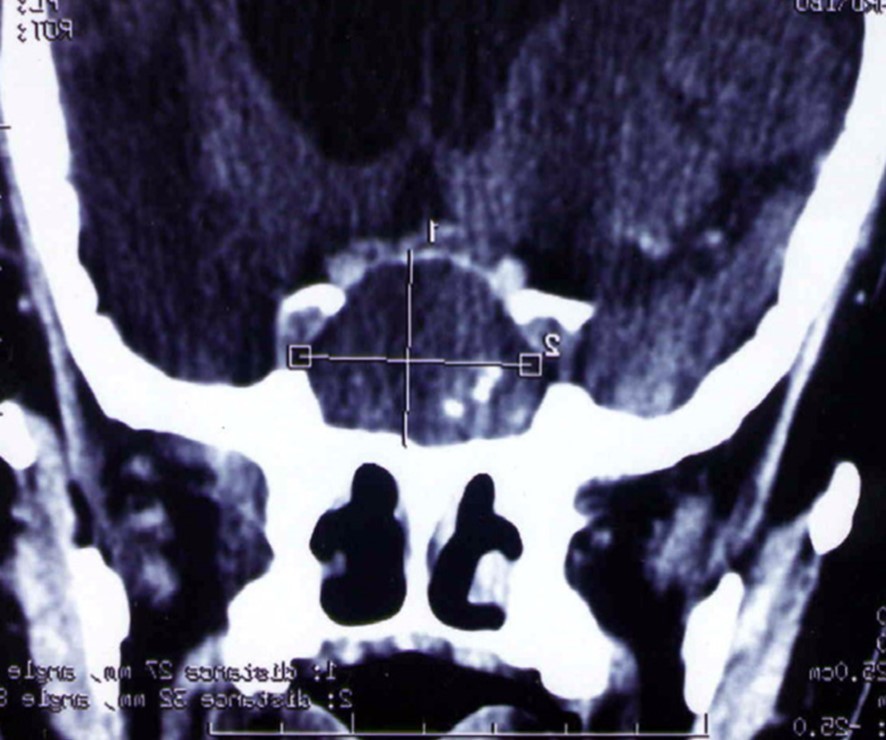

A 65 year-old man presented with progressive visual decrease and ptosis in the left eye. Neurological examination revealed paresis of the 3rd left cranial nerve. Fundoscopy revealed bilateral papillary paleness and visual acuity was: 4/10 at left; 7/10 at right. No signs of endocrine insufficiency or hypersecretion were assessed. There was no evidence of sinusitis. Chest X-ray, routine laboratory investigations and hormonal blood tests were normal. A CT scan showed a hypodense mass enlarging the sphenoid sinus and sellar region with calcification like images and bone erosion of the sellar floor (Figure 5). MRI showed a mass of 26 mm x 33 mm x 25 mm in the sphenoidal sinus ans sellar region, with hypersignal intensity in T1-weighted (Figure 6A) ans T2-weighted sequences, and hyposignal zone in T2-weighted sequences (Figure 6B). Imaging investigations were suggestive of unusual pituitary macroadenoma. The patient underwent a transnasal transsphenoidal approach for excision of the mass. A yellow-brownish gluey material with gummy debris was aspirated from the sphenoid sinus, which was completely cleaned. The sellar floor was eroded which allowed a view of the intact inflammatory dura. An intra-operative presumptive diagnosis was made of caseating granuloma (i.e tuberculosis). The post-operative course was uneventful: the patient recovered from ptosis and visual acuity improve at discharge. Mycobacterium tuberculosis could not be cultured from specimens; and cultures on Sabouraud’s medium did not isolate Aspergillus. Pathologic findings were of non invasive aspergillosis, with many septated fungal hyphae being present without tissue invasion. The patient was not given antifungal drugs because the intrasphenoidal material was completely aspirated. At 6 month and 18 months follow up, the patient had no neurological complaint. No recurrence was observed on control CT scans.

Figure 5.CT scan showing a hypodense mass enlarging the sphenoid sinus and sellar region with calcification like images and bone erosion of the sellar floor

Figure 6.(a) Sagittal T1-weighted MRI showing a well circumscribed hyperintense process in the sphenoidal sinus and sellar region; (b) parasagittal T2-weighted MRI showing a regular hypointense zone into the hyperintense process which is specific to aspergillus infection and corresponds to iron accumulation